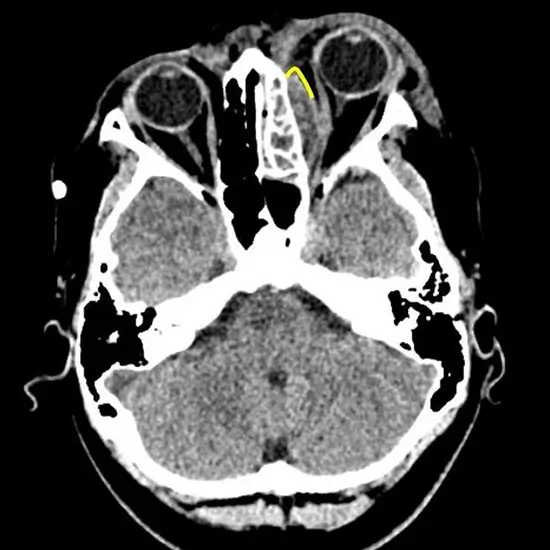

A CT(computed Tomography) Head and Left Orbit is an imaging procedure that is used to create a picture of both the head and left orbit.  It is used to evaluate the brain, brain stem, skull, left eye and left orbital socket for detecting issues and abnormalities.

• Stroke, trauma, congenital defects, bleeding, suspected masses in the brain

• Injury,  congenital effects, broken left eye socket bone, presence of foreign objects in the left eye socket.

• Infection in the eye area

• Nerve supply problem in optic nerve

• The problem is in blood vessels as well as left eye muscles.